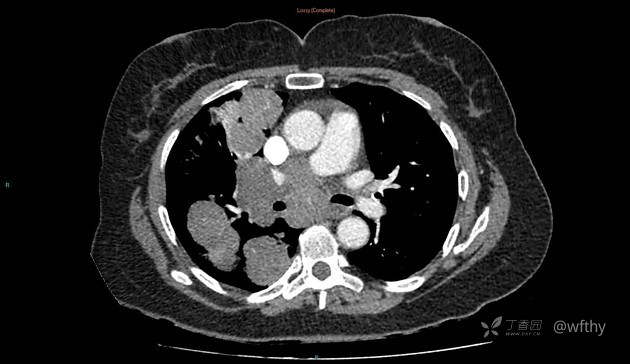

病例女65,头部肿块